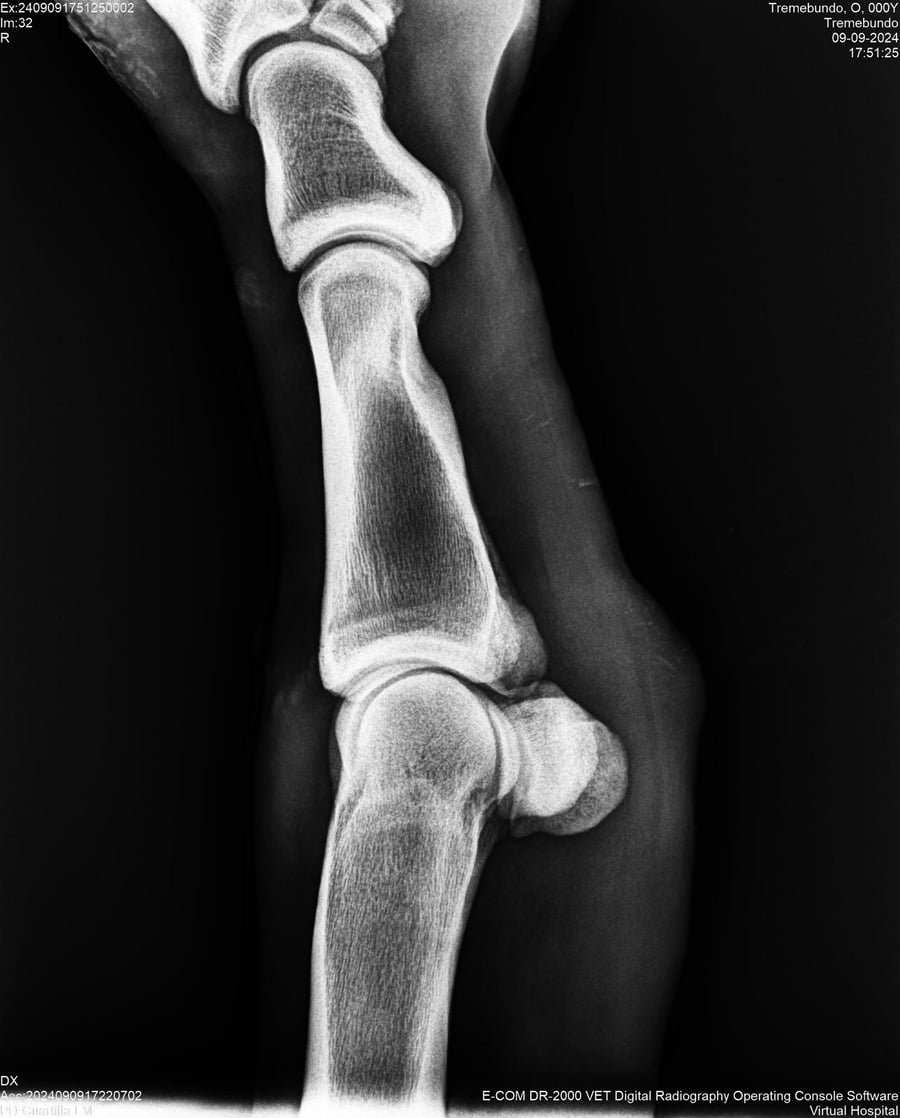

LOTE 37, TREMEBUNDO

Identificador: #291140-

Generacion 2022